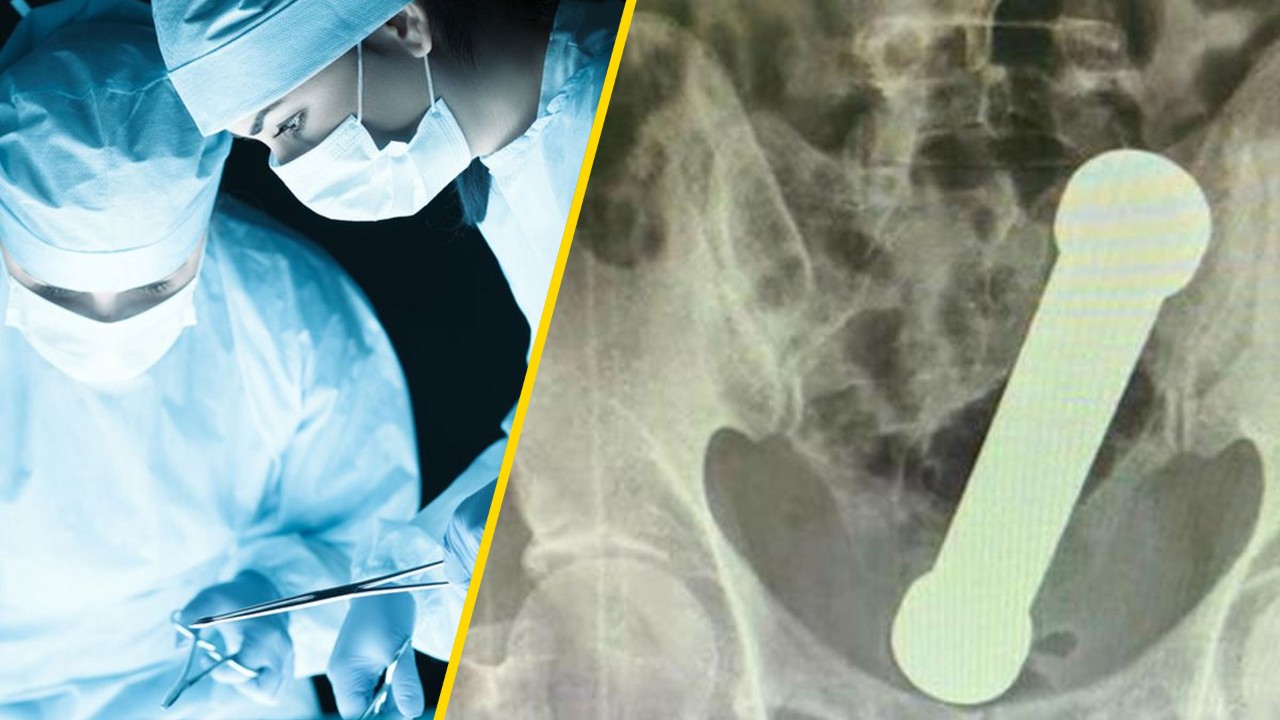

Doctors in Brazil had to remove a 2kg dumbbell that was stuck in a man's rectum, according to a recent case in the International Journal of Surgery Case Reports.

The 54-year-old man waited two days to seek medical help, despite suffering stomach pains, nausea and constipation. He also tried to remove the dumbbell himself. When that failed, he went to the hospital, where doctors initially were unable to find the problem by rectal examiniation.

After X-rays were conducted, doctors found the 20cm -long-dumbbell wedged in where the colon meets the rectum. Ya can't miss it.